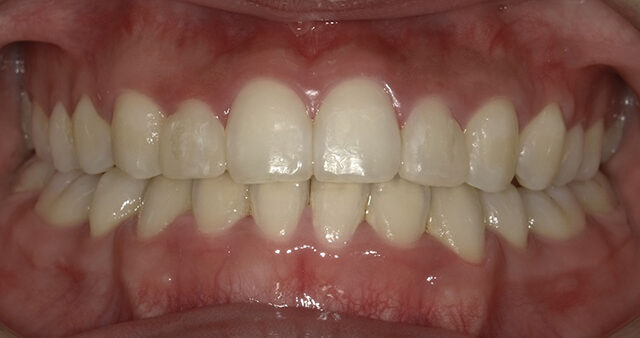

現在の矯正歯科の治療技術は進歩しており、成人の方でも無理なく矯正治療を行えるようになっています。確かに、お子さんの方が成長期にあるためスムーズに治療を行うことができますが、成長期以降の成人の方でも、多少時間はかかるものの、歯並びや噛み合わせのお悩みを解決することは可能です。矯正の大きな目的には、見た目のコンプレックスの解消がありますが、そのほかにも、きれいな歯並びになることで、歯みがきがしやすくなり、むし歯や歯周病の予防につながります。また、噛み合わせが整うことで、筋肉や顎関節、歯周組織に余計な負担をかけずにすみ、全身の健康にもつながります。

健康的で美しい口元になって、明るい笑顔で毎日を過ごしましょう!